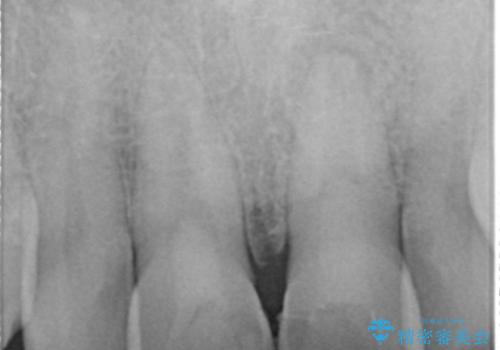

X線写真より、根尖部に透過像が認められ根管治療・ファイバーコア築盛・セラミッククラウンの作製が必要な状態です。

歯ぐきからの出血・排膿がある場合、根管内の感染や 歯肉炎・歯の破折などが考えられます。

X線検査や歯周組織検査などを行い適切な治療を行うことで良好な結果を得ることができます。